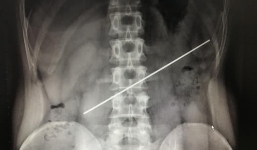

Nuốt thanh thép gần 20 cm vì cá cược 18 triệu đồng và cái giá đắt

27-04-2018 | 10:37